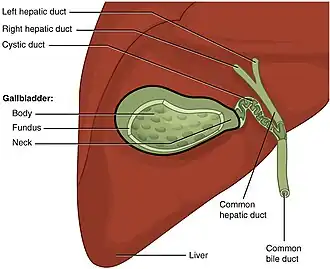

Cholecystectomy is the surgical removal of the gallbladder. Cholecystectomy is a common treatment of symptomatic gallstones and other gallbladder conditions.[1] In 2011, cholecystectomy was the eighth most common operating room procedure performed in hospitals in the United States.[2] Cholecystectomy can be performed either laparoscopically or through a laparotomy.[3]

Pain and complications caused by gallstones are the most common reasons for removal of the gallbladder.[6] The gallbladder can also be removed in order to treat biliary dyskinesia or gallbladder cancer.[7]

Biliary colic, or pain caused by gallstones, occurs when a gallstone temporarily blocks the bile duct that drains the gallbladder.[11] Typically, pain from biliary colic is felt in the right upper part of the abdomen, is moderate to severe, and goes away on its own after a few hours when the stone is either passed or dislodges.[12] Biliary colic usually occurs after meals when the gallbladder contracts to push bile out into the digestive tract. After a first attack of biliary colic, more than 90% of people will have a repeat attack in the next 10 years.[1] Repeated attacks of biliary colic are the most common reason for removing the gallbladder, and lead to about 300,000 cholecystectomies in the US each year.[10][13]

Cholecystitis, or inflammation of the gallbladder caused by interruption in the normal flow of bile, is another reason for cholecystectomy.[14] It is the most common complication of gallstones; 90–95% of acute cholecystitis is caused by gallstones blocking drainage of the gallbladder.[15] If the blockage is incomplete and the stone passes quickly, the person experiences biliary colic. If the gallbladder is completely blocked and remains so for a prolonged period, the person develops acute cholecystitis.[16]

Cholangitis and gallstone pancreatitis

Cholangitis and gallstone pancreatitis are rarer and more serious complications from gallstone disease. Both can occur if gallstones leave the gallbladder, pass through the cystic duct, and get stuck in the common bile duct. The common bile duct drains the liver and pancreas, and a blockage there can lead to inflammation and infection in both the pancreas and biliary system. While cholecystectomy is not usually the immediate treatment choice for either of these conditions, it is often recommended to prevent repeat episodes from additional gallstones getting stuck.[14]: 940, 1017